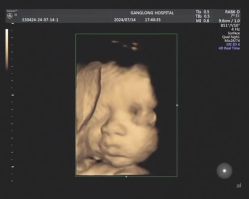

• 深圳港龙妇产医院

• -深圳港龙妇产医院

容易生气的小果果 上传于 25-08-30 | 报错

相册